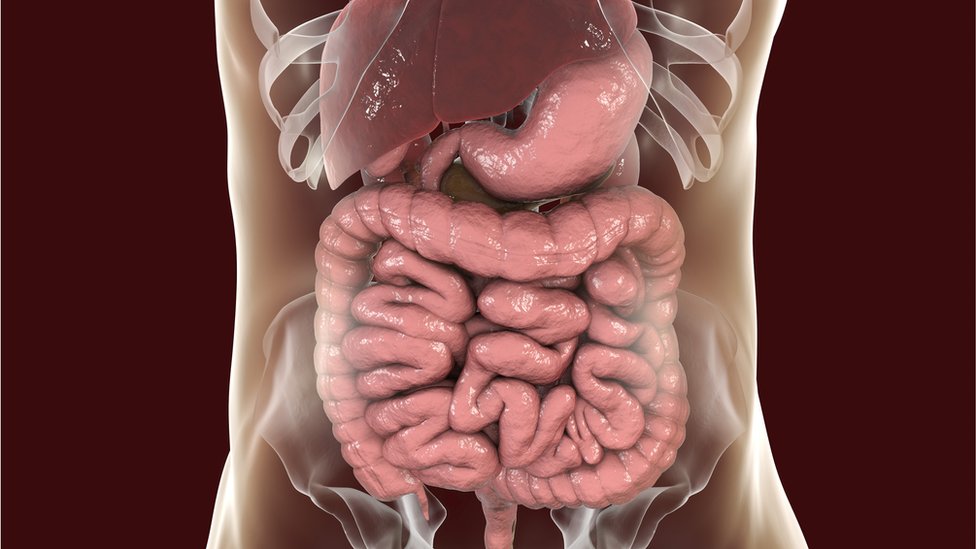

Njene fekalije, udružene sa „dobroćudnim“ bakterijama, biće pomešane sa izmetom bolesnika, kako bi pomogle u oporavku crevnog sistema.

Naša creva si domaćini milionima bakterija koje žive u zajednici. Ovi različiti mikrobiomi su jedinstveni za svakog od nas – ne postoje dva identična.

O’Salivenova istraživanja, objavljena u časopisu Granice u ćelisjkosj i infektivnoj mikrobiologiji, ukazuju da bipostojanje mnoštva mikroorganizama u izmetu moglo da bude prednost.

Kaže da veliki broj mikroorganizama pronađenih u izmetu donora predstavlja ključan faktor u efikasnosti transplantacije fekalija. I pacijenti koji dobro reaguju na transplantaciju takođe razviju mnogo raznovrsnije mikrobiome.

I možda se ne radi samo o tome koja je bakterija prisutna u izmetu.

„Neki slučajevi dijareje koja se konstantno vraćala su izlečeni transplantacijom filtriranih fekalija, kojima su sve žive bakterije isfiltrirane, ali su sadržale DNK i viruse.“

„Ovi virusi bi mogli da utiču na opstanak i metaboličke funkcije presađenih bakterija i ostalih mikroba“, kaže doktor O’Saliven.

Trenutno, većina fekalija se koristi za lečenje opasne crevne infekcije izazvane bakterijom clostridium difficile.

Ova infekcija može nastupiti kada pacijentove „dobre“ bakterije budu uništene antibioticima. Za najosetljivije pacijente, može biti čak i smrtonosna.

Istraživanja doktorke Mekdonald ukazuju da transplanti kake imaju posebnu ulogu, nadoknađujući ono što je bolest odnela.